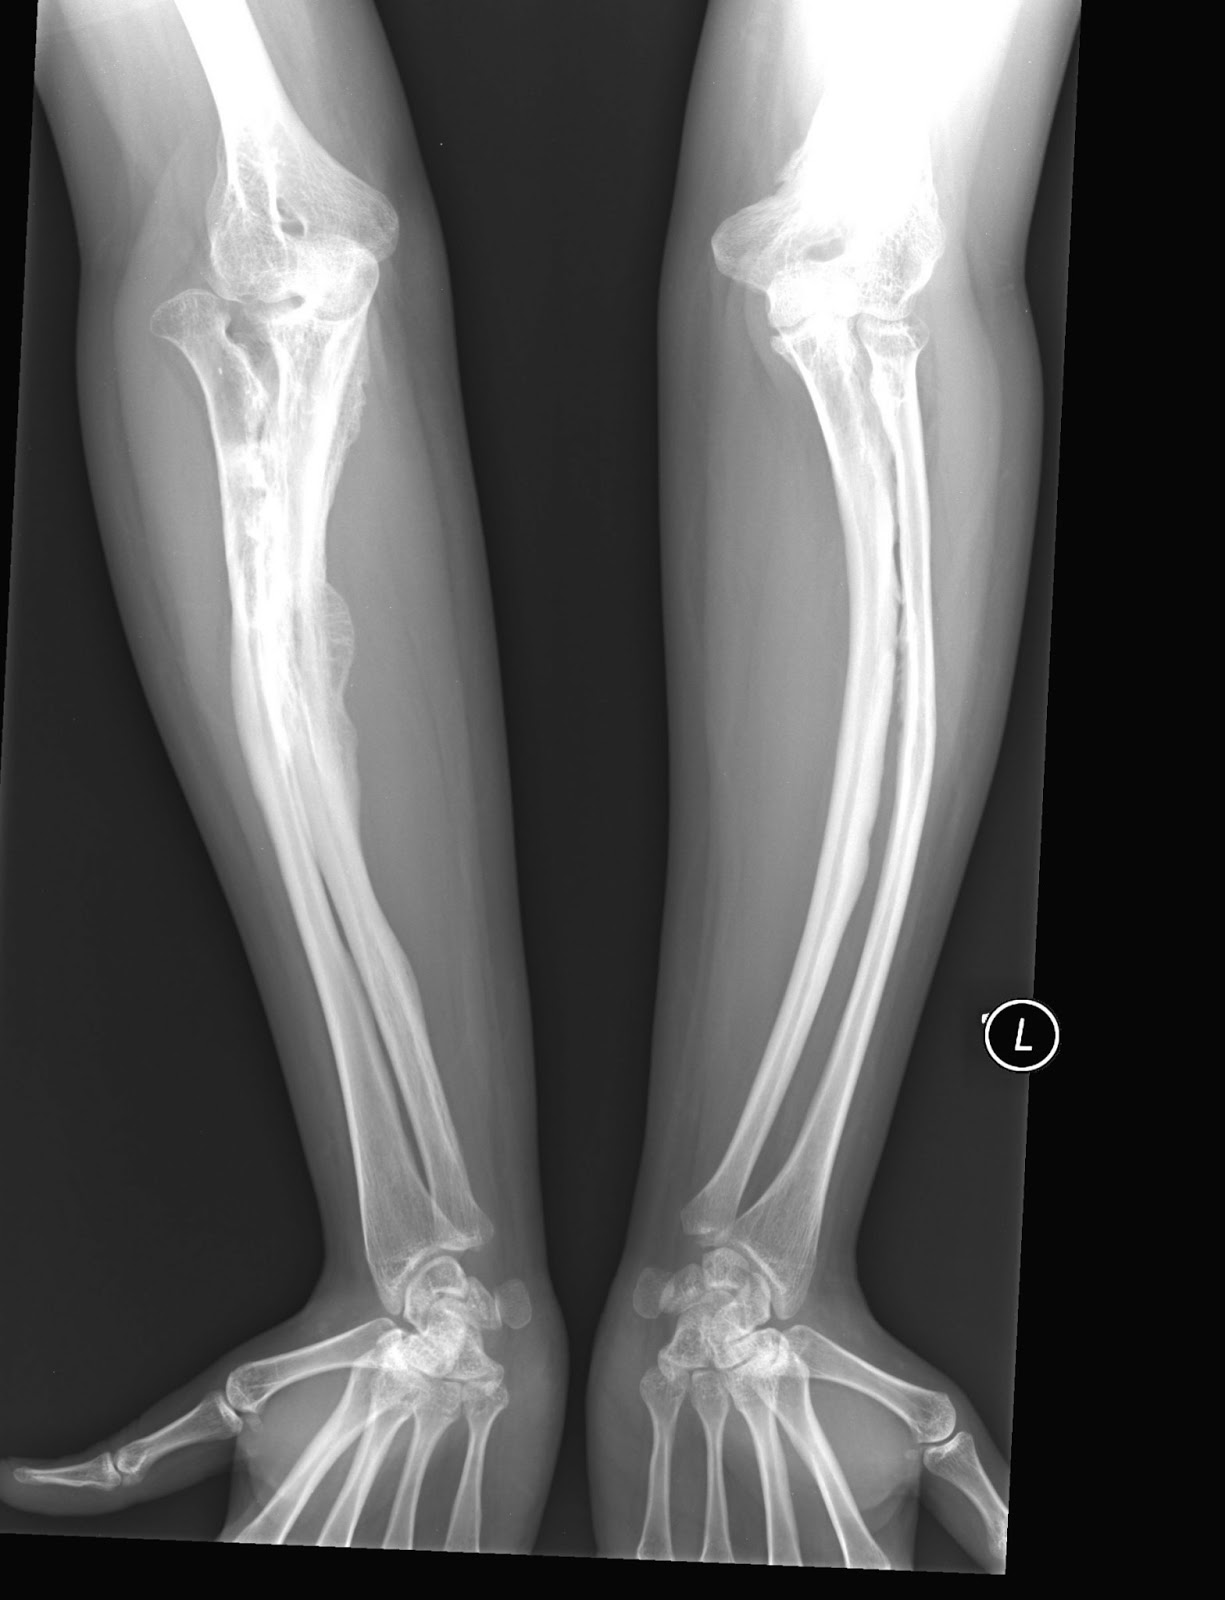

From radiologypics.com

Osteogenesis Imperfecta Osteogenesis Imperfecta Or Brittle Bones It is sometimes known as brittle bone disease. Oi is also called brittle bone disease. A child born with oi may have soft bones that break (fracture) easily, bones that are not formed normally, and other problems. Osteogenesis imperfecta (oi), also known as brittle bone disease or brittle bone dysplasia, most commonly presents in children. Oi is caused by faults. Osteogenesis Imperfecta Or Brittle Bones.

From www.sciencephoto.com

Brittle Bone Disease, Xray Stock Image C036/5861 Science Photo Osteogenesis Imperfecta Or Brittle Bones Osteogenesis imperfecta (oi) is a disease that causes your bones to break (fracture) easily. Oi is caused by faults or 'mutations' in the genes that control the production of collagen. It is sometimes known as brittle bone disease. It is also known as brittle bone disease. Osteogenesis imperfecta (oi), or brittle bone disease, is a heterogeneous disorder characterised by bone. Osteogenesis Imperfecta Or Brittle Bones.